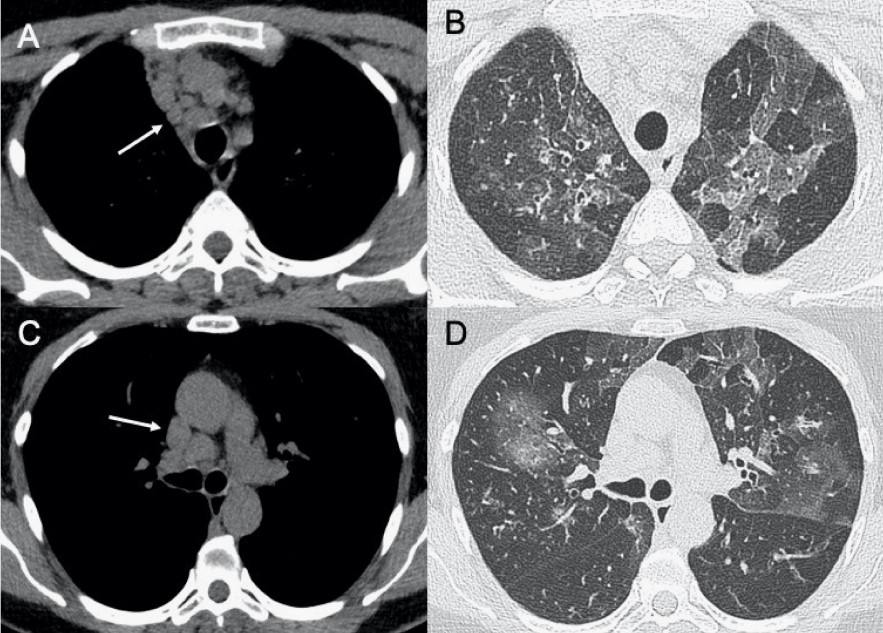

?EB病毒

● CXR:淋巴結(jié)腫大,雙肺間質(zhì)實(shí)質(zhì)受累。

● CT:淋巴結(jié)腫大和較少見(jiàn)的間質(zhì)浸潤(rùn)伴彌漫性GGO和實(shí)變。

圖9 EB病毒性肺炎。圖(A,C)顯示縱隔淋巴結(jié)腫大(箭頭),與雙肺局灶性小葉GGO相關(guān)(B,D)。